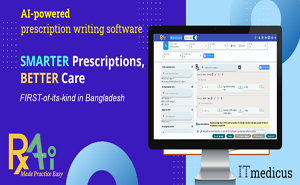

This AI-powered prescription-writing software is designed to

understand a patient’s clinical condition and assist doctors in making efficient, informed decisions about the disease.This

software helps Doctors --

To create prescriptions SMARTLY and QUICKLY

-

To make decisions INTELLIGENTLY and ACCURATELY REGISTER NOW!

RxAi recommends

optimal treatments based on current guidelines and patient profiles, enhancing

clinical workflow and reducing prescription times.This is not only

prescription-writing software. Instead, it understands the patient's clinical

condition and assists physicians in making informed decisions about the

disease.“AI-supported

decisions...